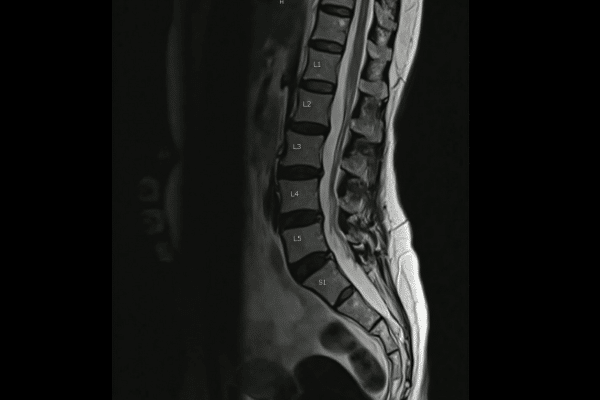

Spondylolysis occurs when a stress fracture or defect develops in the pars interarticularis, a small piece of bone that connects the vertebrae in the lower back. This condition often affects the L5 vertebra and may be present on one or both sides of the spine. In some cases, spondylolysis can progress to spondylolisthesis, which is when the vertebra slips forward out of normal alignment.